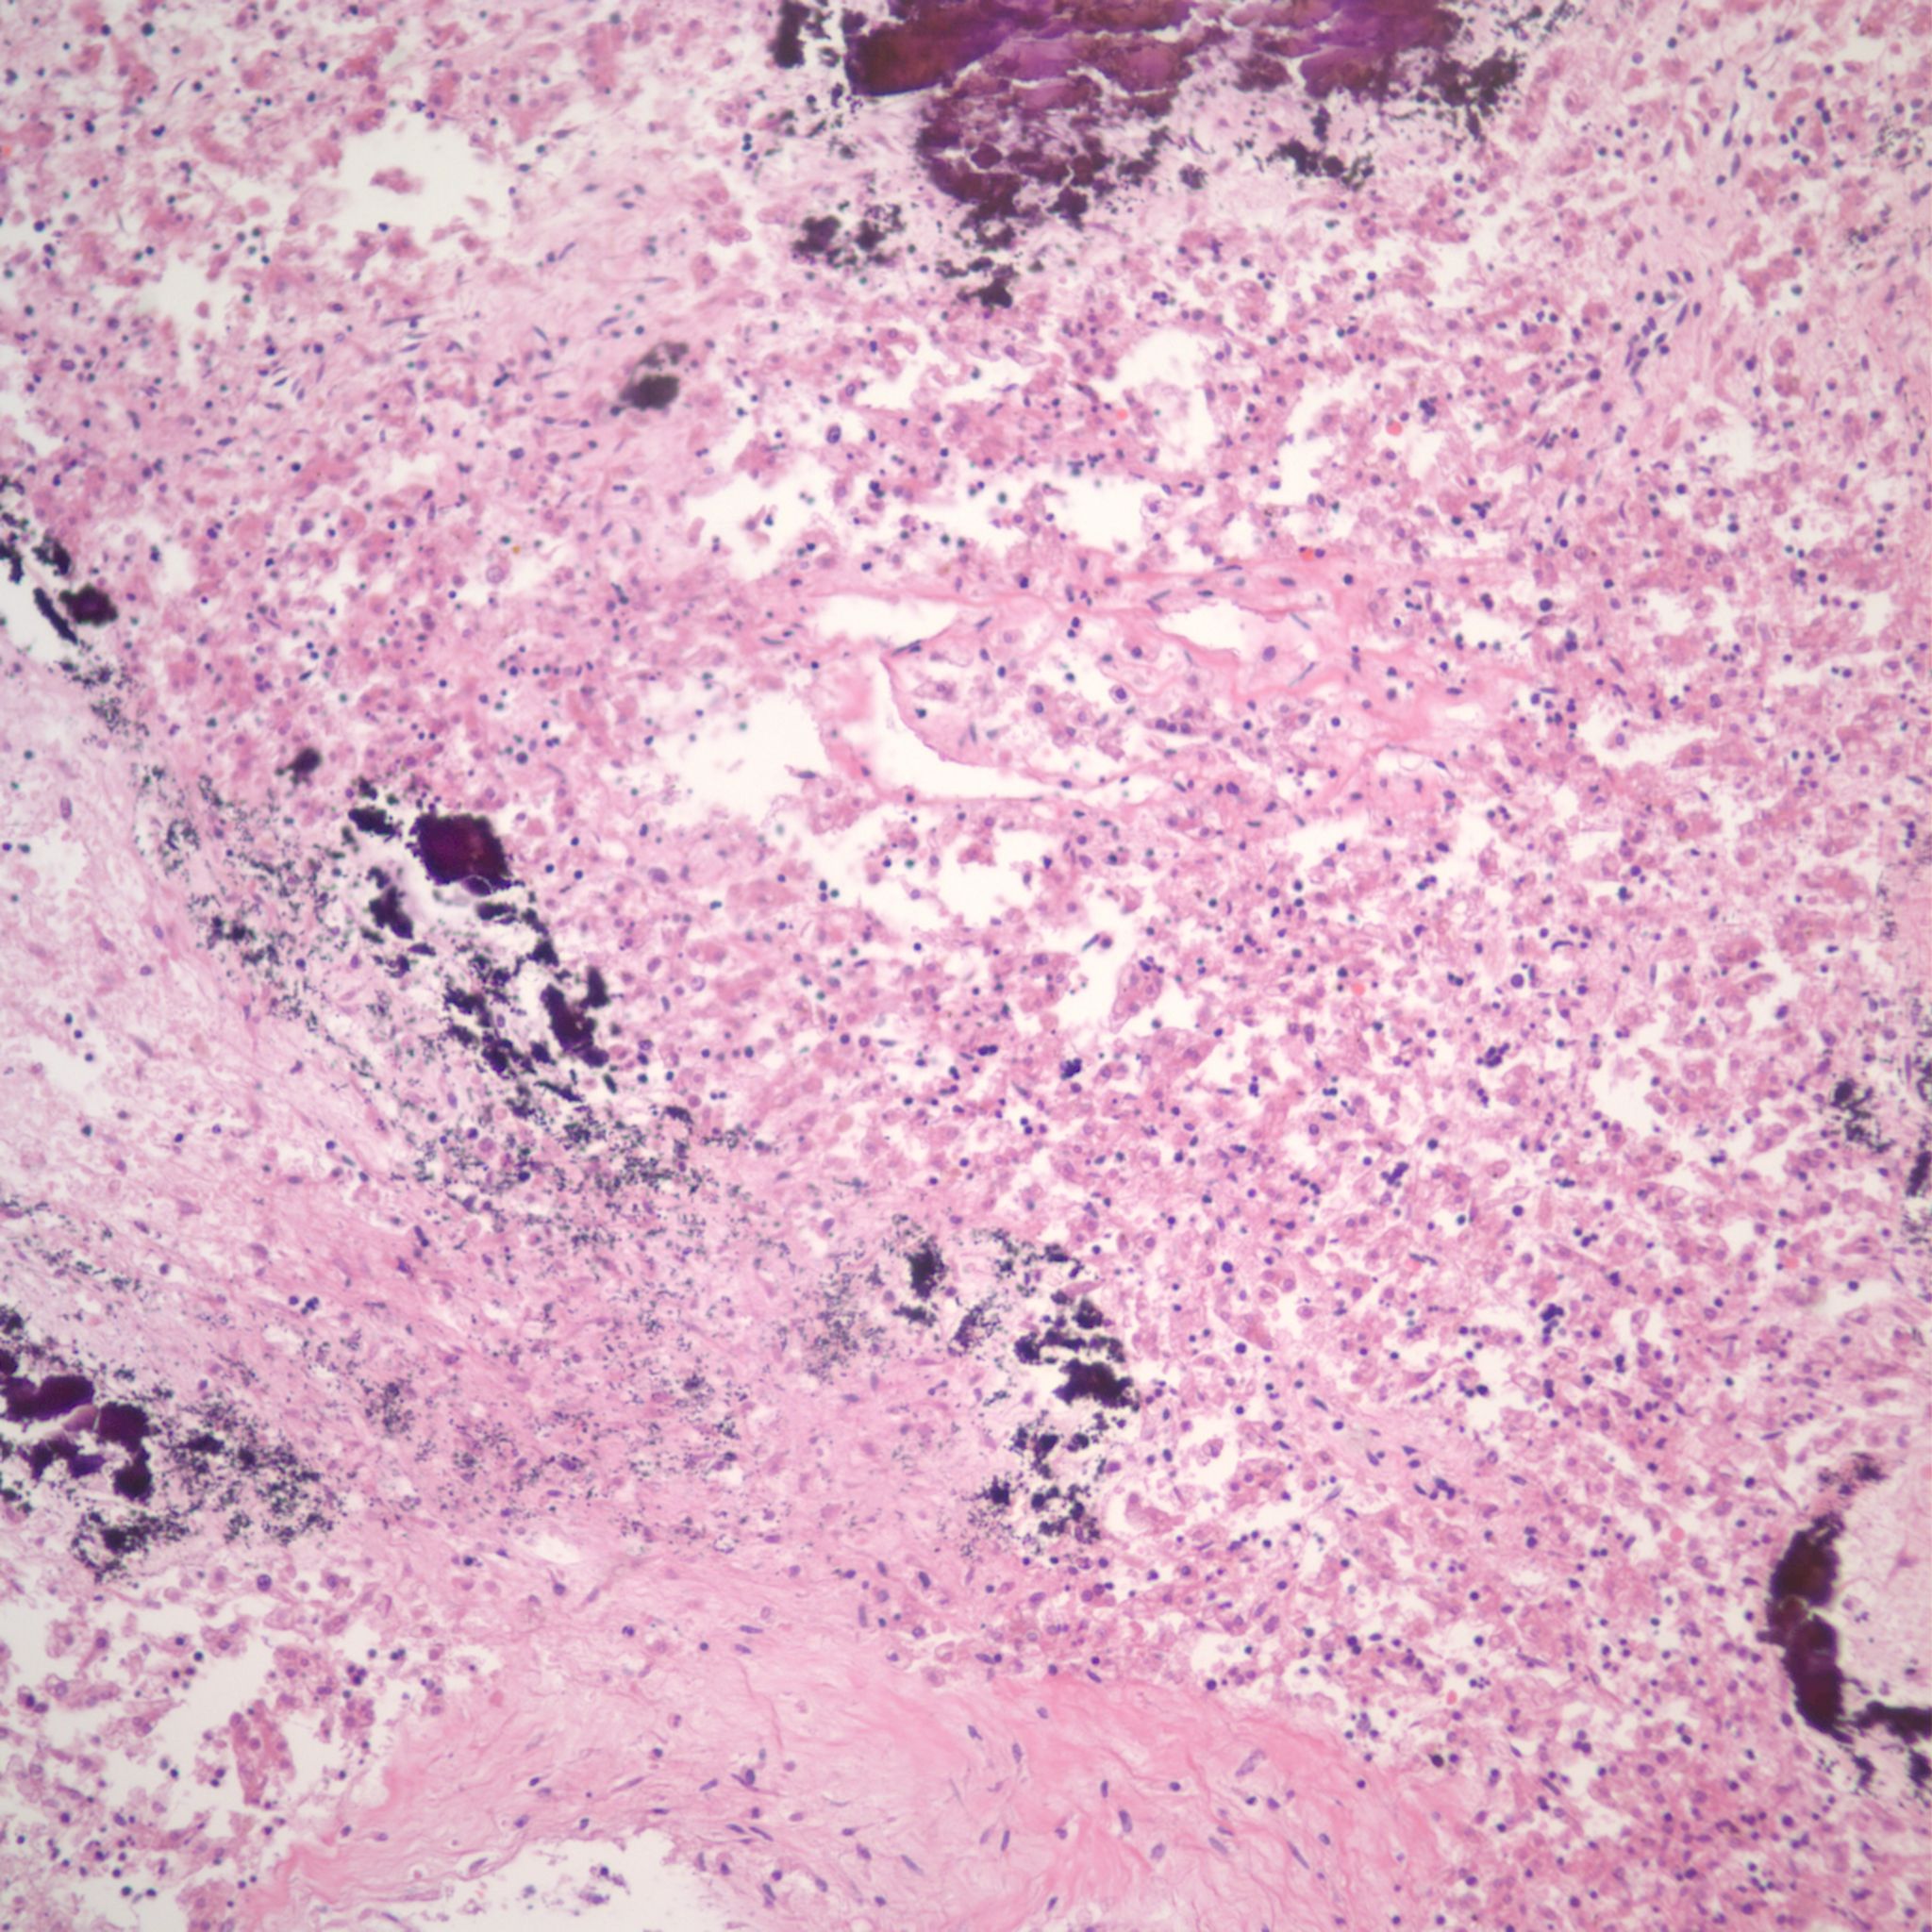

Hemorrhage can occur in the liver as in other organs with fetal septic shock presumably from disseminated intravascular coagulation, although D dimers or other evidence is not available (Fig 12).

More cryptic in origin are focal subcapsular and periportal hemorrhages seen usually in early gestation fetuses that can be seen on fine grained postmortem radiographs (Fig 13a)9. These lesions may stain for both hemosiderin and calcium. (Fig 13b, c)